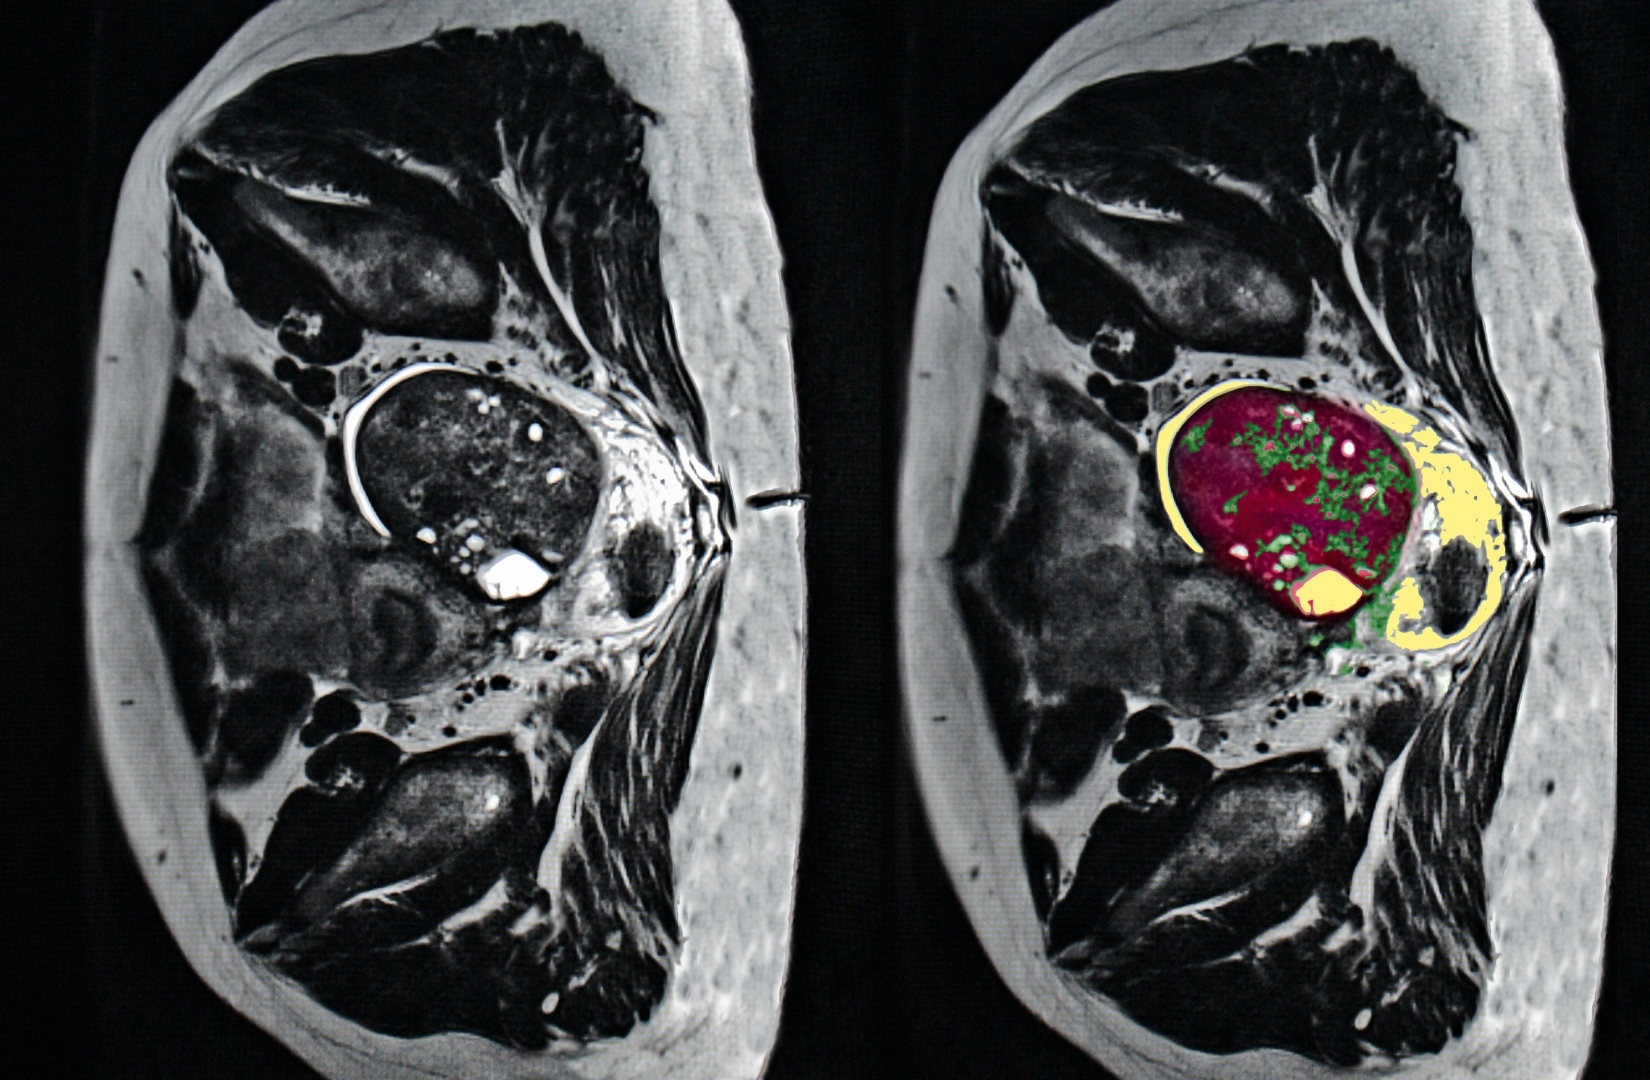

Câncer de Ovário

O câncer de ovário, em sua forma mais comum (carcinoma seroso de alto grau), é um dos mais desafiadores porque costuma evoluir silenciosamente. Muitas vezes, os sintomas iniciais são confundidos com alterações digestivas ou hormonais comuns, o que pode atrasar o diagnóstico.

Ele pode se originar nos ovários ou nas tubas uterinas e passar para outros órgãos da pelve e do abdome. Com frequência, a estratégia de tratamento envolve uma cirurgia citorredutora mais extensa. A experiência da equipe e a abordagem multidisciplinar influenciam diretamente nos desfechos da paciente.

Tratamento das Doenças de Disseminação Peritoneal

O peritônio é uma membrana fina que reveste os órgãos abdominais e pode ser afetado por diversos tipos de tumores, incluindo os ginecológicos. A disseminação peritoneal ocorre quando células tumorais se espalham por essa membrana, exigindo uma abordagem cirúrgica altamente especializada.

Atualmente, o tratamento da disseminação peritoneal tem avançado significativamente, e a cirurgia citorredutora associada a técnicas como HIPEC (quimioterapia intraperitoneal hipertérmica) tem mostrado benefícios importantes para determinados pacientes.

Cirurgia citorredutora (CRS) – remoção cirúrgica das áreas afetadas pelo tumor no peritônio.

HIPEC (Quimioterapia Intraperitoneal Hipertérmica) – aplicação de quimioterapia aquecida na cavidade abdominal ao final da cirurgia para eliminar células tumorais residuais.